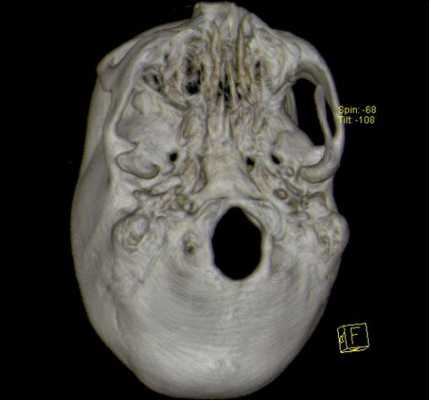

3D-реконструкция с помощью компьютерной томографии

Трехмерные реконструкции, выполненные с помощью КТ